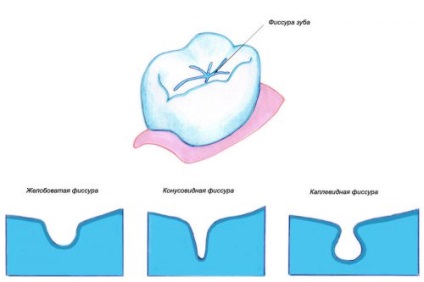

fogak hasadék - ez anatómiai mélyedések a felszínükön, gyakran egyenetlen, van horonnyal vagy barázdákat. A legtöbb nagy repedések a rágás zápfog. Egyszerűen fogalmazva, a felszín alatt repedések megérteni a fogak, amely közvetlen érintkezésbe az élelmiszerrel.

Típusai hasadék formájától függően